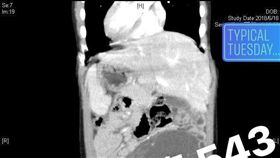

女嬰肺炎送急診 驚見內臟如鏡面相反

中國大陸江蘇省揚州市有一名出生僅1個月的女嬰,因為肺...